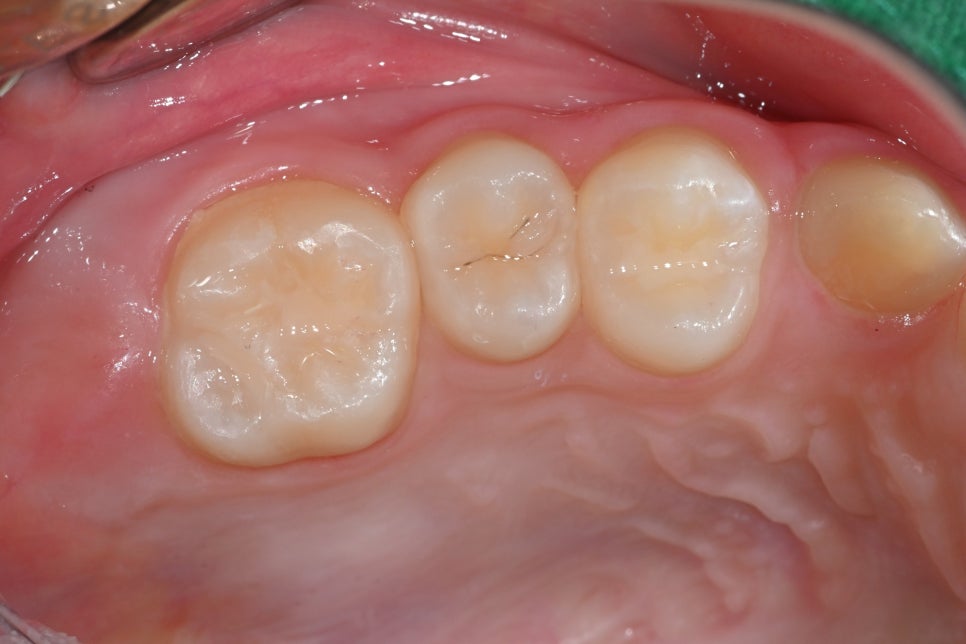

✅ After Treatment Photo (03.18)

This is the naturally restored appearance of the molar after insurance-covered resin restoration.

The treatment was performed as an insurance-covered resin restoration, allowing the patient to continue daily life without pain and restoring the tooth very naturally in appearance as well.